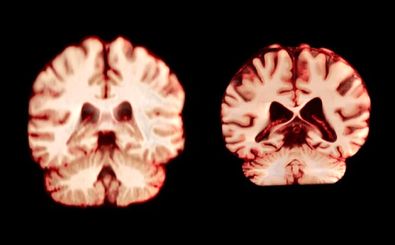

پژوهشی تازه نشان میدهد که تصاویر معمولی از مغز میتوانند نشانههایی از سرعت پیری زیستی در خود داشته باشند؛ از جمله…